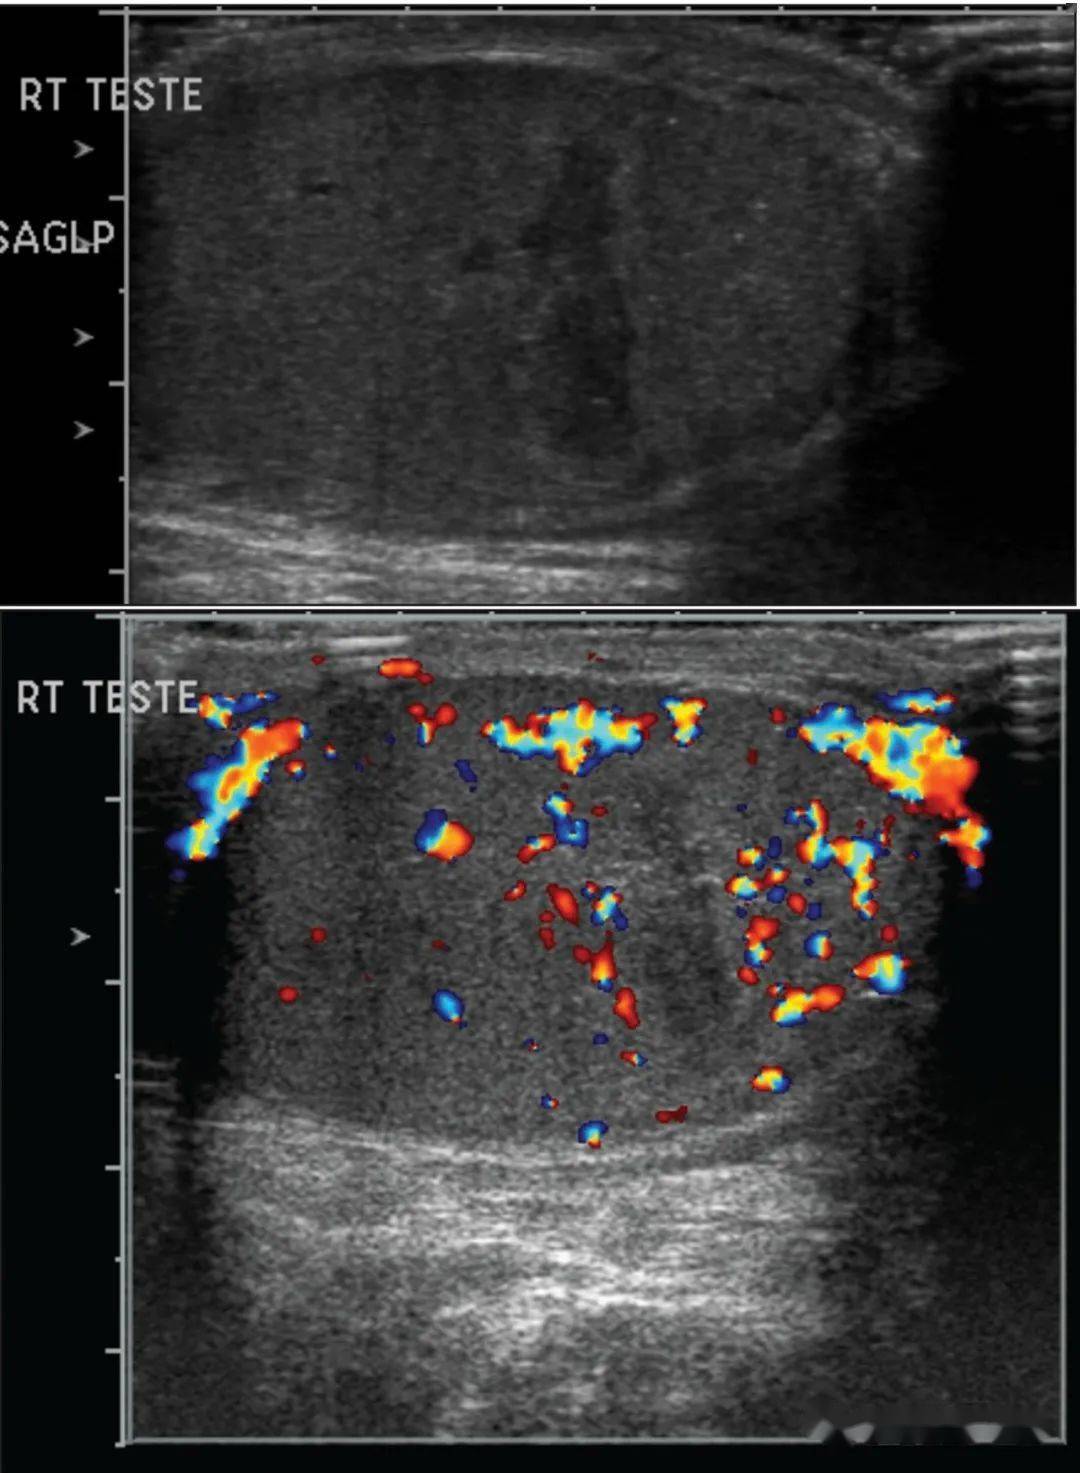

各位看看这个睾丸彩超只是单纯的附睾炎吗

图片尺寸3264x1836